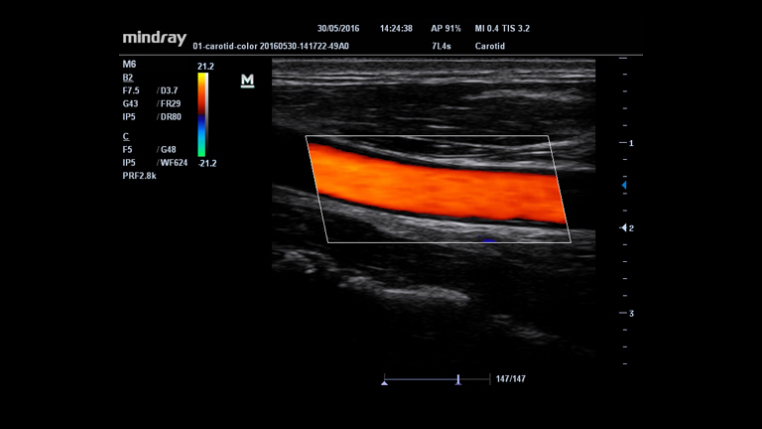

- HR Flow™: Tecnologia avançada para visualização detalhada de vasos sanguíneos pequenos.

- IMT (Medição da Espessura Íntima-Média): Mede automaticamente a parede das artérias, auxiliando em exames cardiovasculares.

- Lineares: L14-6Ns, L14-6s, 7L4s.